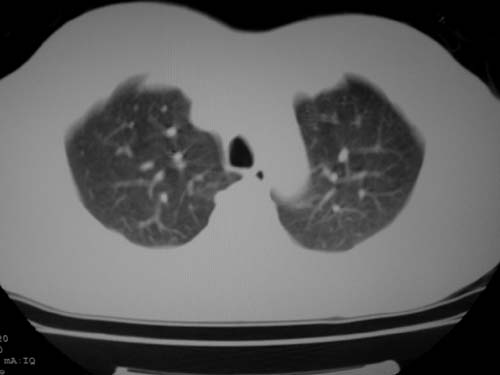

标题: CT19540: 31岁。自述结核性胸水治疗两个月后,在外院拍x线发 [打印本页]

标题: CT19540: 31岁。自述结核性胸水治疗两个月后,在外院拍x线发

右侧胸壁结节状软组织影伴相应肺叶内受侵,伴右侧胸腔积液。考虑:结核性可能大。

1、炎性包块;2、右侧少量胸膜积液。

1、炎性病变,结核可能;2、右侧少量胸膜积液。

病灶也是发生于结核球好发部位,支持结核

考虑结核性结节

多考虑包裹性胸腔识液。

右侧胸壁结节状软组织影伴相应肺叶内受侵,伴右侧胸腔积液,结合临床,首先考虑结核。

考虑结核性胸膜炎,胸膜肥厚,不除外胸膜间皮瘤可能,建议复查。

支持结核,胸膜间皮瘤不排除.

1)考虑右侧结核性胸膜结节。2)右侧胸膜增厚+包裹性胸腔积液。

结核性脓胸、肺内结核?